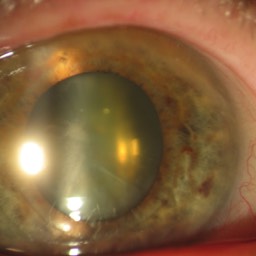

Quelques pathologies ophtalmologiques du segment antérieur